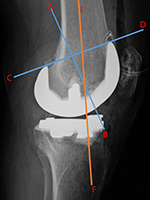

| Total Knee arthroplasty (TKA) Evaluation |

| 67 year-old woman. Postoperative images of a Biomet XPA Bicruciate Preserving TKA. Same patient as above. On the AP view (left image) the femorotibial angle is the intersection between the femoral anatomic axis (blue line) and the tibial anatomic axis (orange line). The femoral component should be centered along the femoral anatomic axis, and the tibial component should be perpendicular to the tibial anatomic axis. The femorotibilal angle should be 4-7° valgus. On the lateral view (right image) the femoral component should be roughly perpendicular to the femoral anatomic axis (orange line), and the tibial component should be perpendicular to the tibial anatomic axis (blue line) or have slight flexion (3°–6°) [posteriorly sloped]. |

Same patient as left two images. Another way to evaluate the TKA on the lateral view is to draw line C-D through anterior and posterior margins of the femoral component and line A-B perpendicular to line C-D. Line E-F is along the anatomic axis of the femur. The angle between lines A-B and E-F should approximate 30°. |